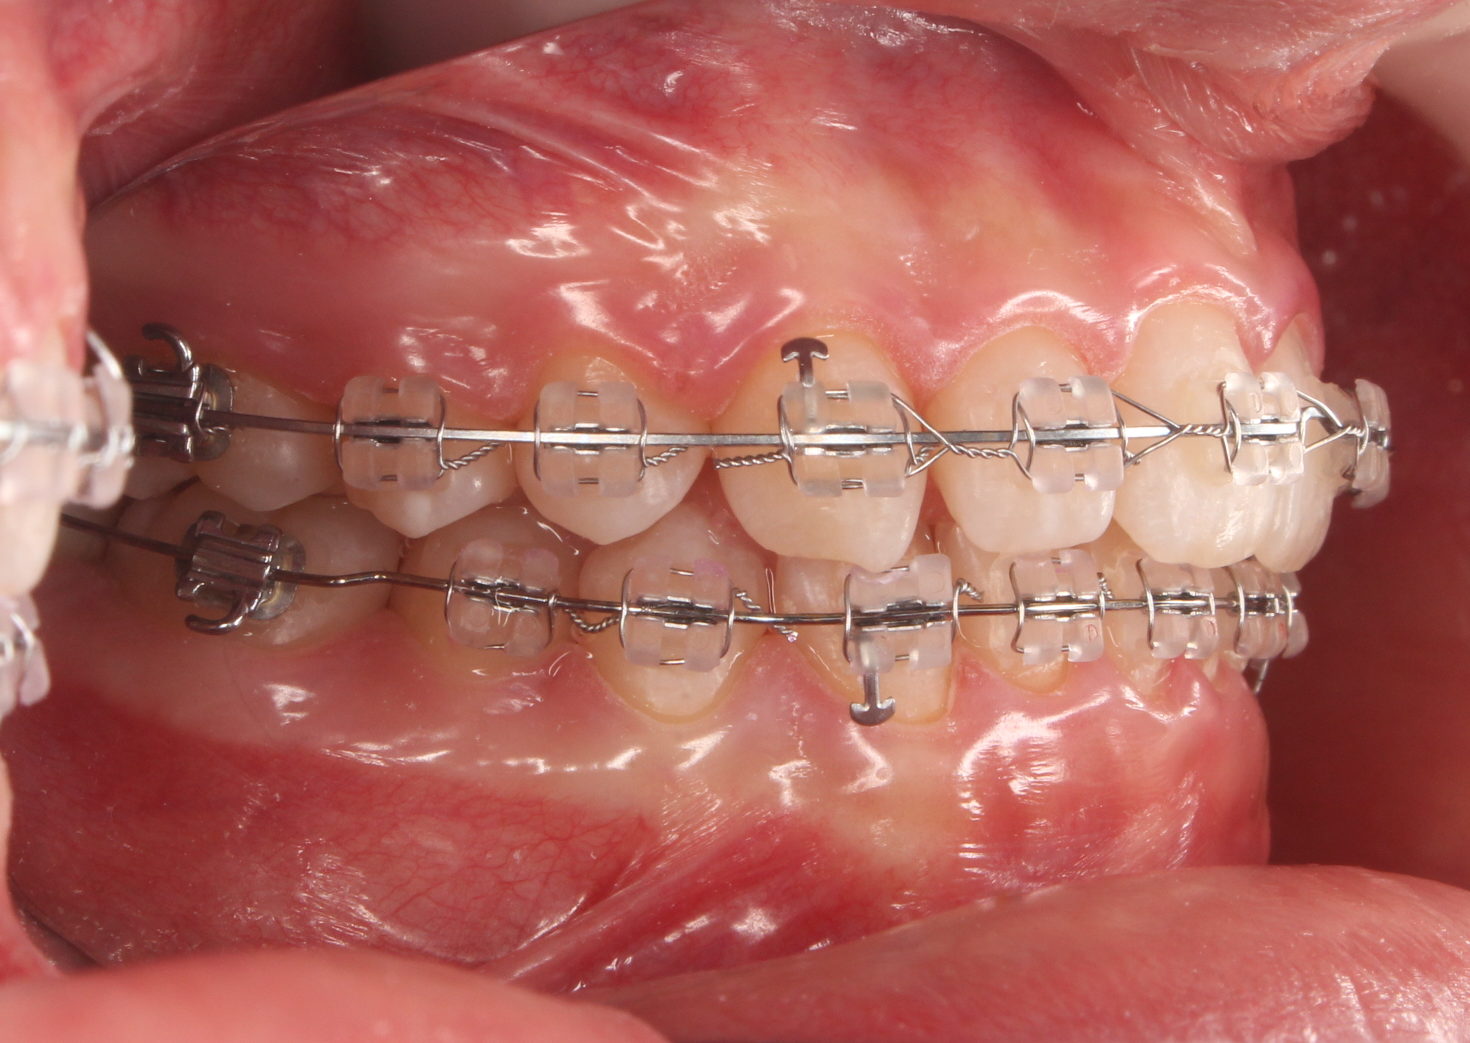

初診の状態です。

過蓋咬合といわれるケースで、下の歯が深く咬み込んでいる状態です。

また前歯に欠損もあり、以前から見た目を気にしていたそうです。